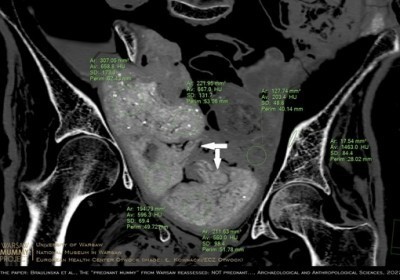

Mumia egipska z Warszawy nie była w ciąży - w jej miednicy znajdują się... pakunki

Nie płód, ale kilka zawiniątek znajduje się w miednicy mumii kobiety prezentowanej w Muzeum Narodowym w Warszawie - dowodzi zespół naukowców. W jednym… Czytaj więcej